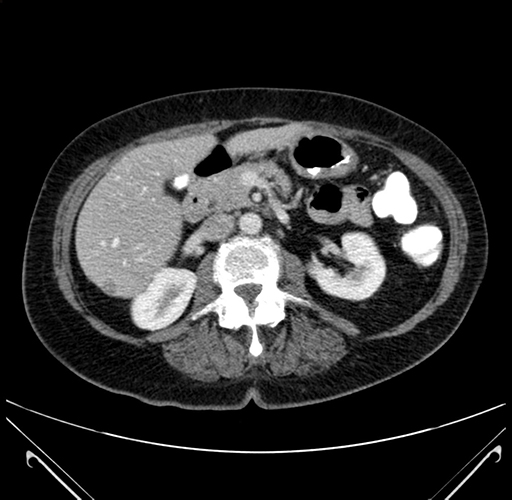

Axial Venous